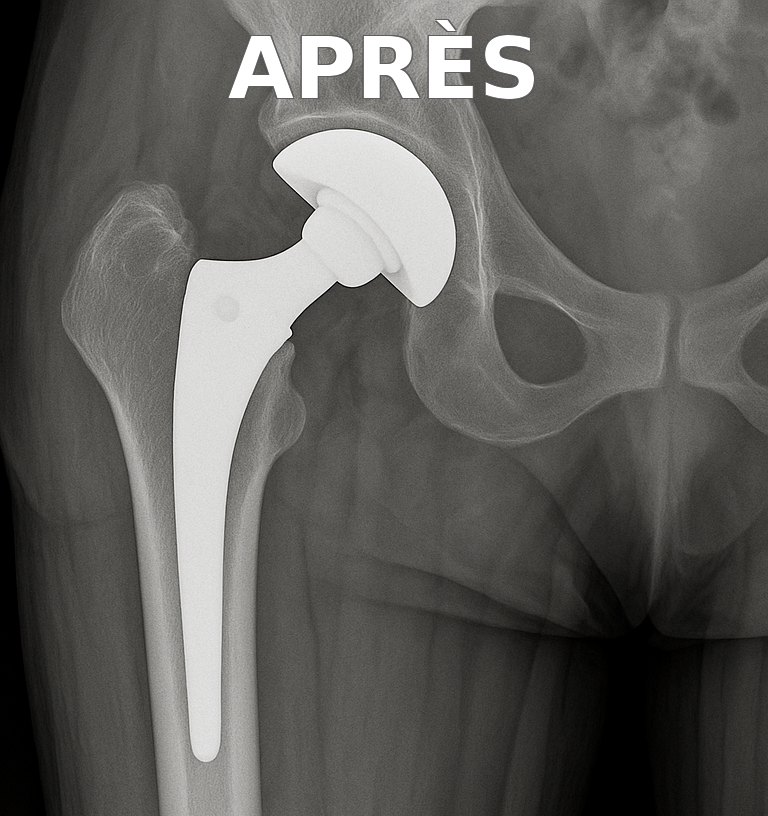

Prothèse de hanche